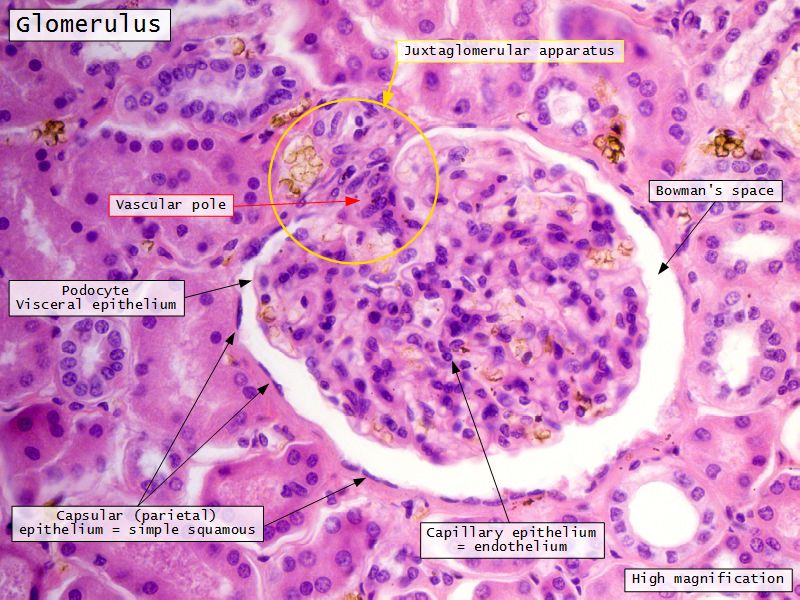

Epithelium layers

- Capillary endothelium

- Visceral layer of epithelium

- Podocytes

- Resting on glomerular basement membrane

- Capsular space

- Parietal layer of epithelium

- Simple squamous epithelium

Juxtaglomerular complex

Area where distal convoluted tubule return to glomerulus and pass through the notch between the afferent and efferent arterioles. Modification of the wall of the tubule and afferent arteriole and presence of specialised cells in the connective tissue.Modifications

- Distal convoluted tubule

- Macula densa

- Narrow epithelial cells

- Nuclei densely packed

- CT cells

- Laci cells

- Similar to mesangial cells

- Afferent arteriole

- Modified smooth muscle cells

- Juxtaglomerular cells

- Secretory function